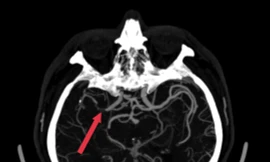

TP - Gần đây Trung tâm Đột quỵ (Bệnh viện Bạch Mai) tiếp nhận nhiều ca đột quỵ có tuổi đời còn rất trẻ (dưới 45 tuổi), chiếm 15% tổng số bệnh nhân của toàn Trung tâm. Xu hướng trẻ hóa đột quỵ tại Việt Nam đang trở thành vấn đề đáng lo ngại.

TPO - Nhập viện trong tình trạng nguy kịch với chẩn đoán bị đột quỵ não, người đàn ông mang quốc tịch Hàn Quốc đối mặt với nguy cơ tử vong. Các bác sĩ đã khẩn cấp thực hiện phương án can thiệp, giúp bệnh nhân vượt qua nguy kịch.